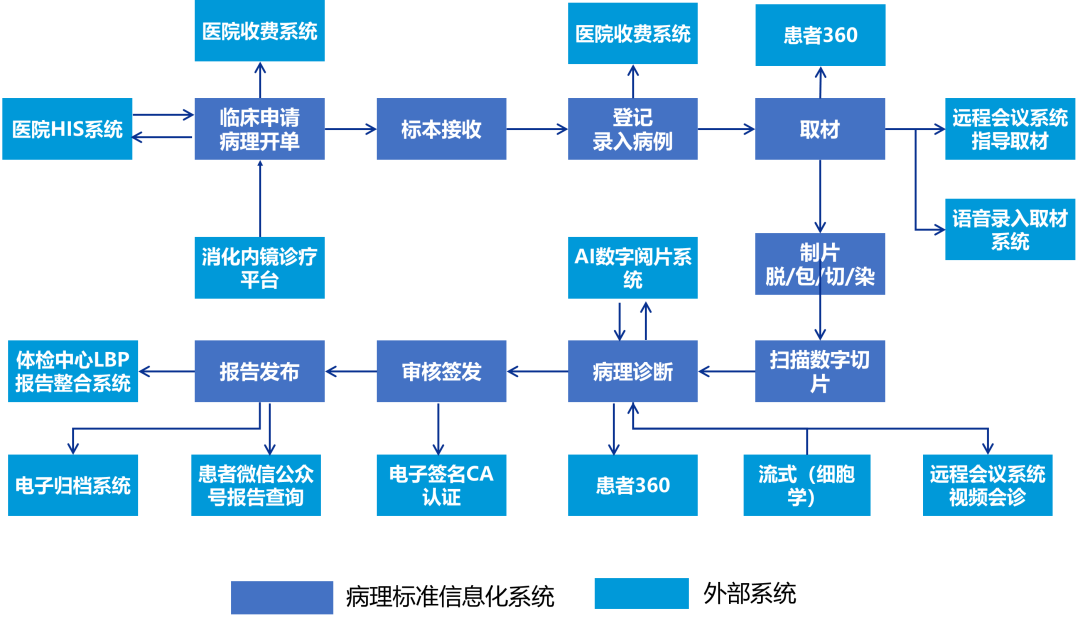

数字化智慧病理科建设全景图

来源:蛋壳研究院

数字化病理科建设模块介绍

数字化建设模块图

来源:蛋壳研究院